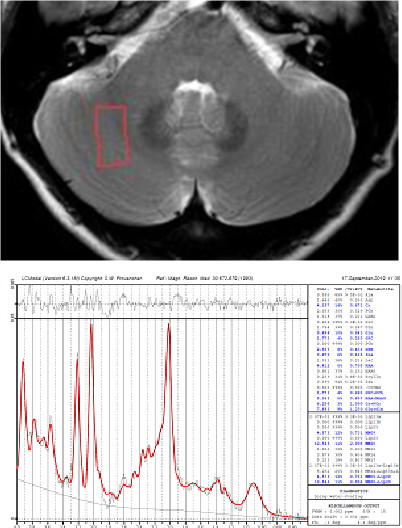

小脳は運動機能や言語機能、眼球運動、平衡機能と密接に関係していることは古くから知られています。また、運動遂行時においては運動の実行と運動肢からのフィードバックの差(誤差)の修正に小脳は重要な役割を果たすことがわかっています。一方、近年の脳機能イメージング技術の発展に伴い、表在感覚である触覚刺激によっても小脳が活動することがわかってきました。しかし、この小脳の活動は、単に擦られる強さに応じて増減するのか、皮膚上を物体が動く方向や速度、擦られる粗さや滑らかさに関係しているのか、より高次な"擦られ心地"のような認知機能と関係しているのかなど、その役割は全くわかっていません。本研究では、脳機能イメージング手法<Functional MRI(図1),Voxel based morphometry (VBM, 図2),MR spectroscopy (MRS, 図3), Functional connectivity解析(図4)など>を駆使して、大脳および小脳の構造解析・機能解析を詳細に行い、皮膚を擦られた際の情報処理に係わる「小脳の役割」を探求していきます。さらに、触覚刺激の物理特性と官能検査による心理特性もあわせて解析することにより、単に表在感覚情報処理にかかわる小脳の役割を解明するだけでなく、アスリートの"研ぎ澄まされた感覚"の神経基盤を解明したいと考えています。

【図3】MRスペクトロスコピーの例